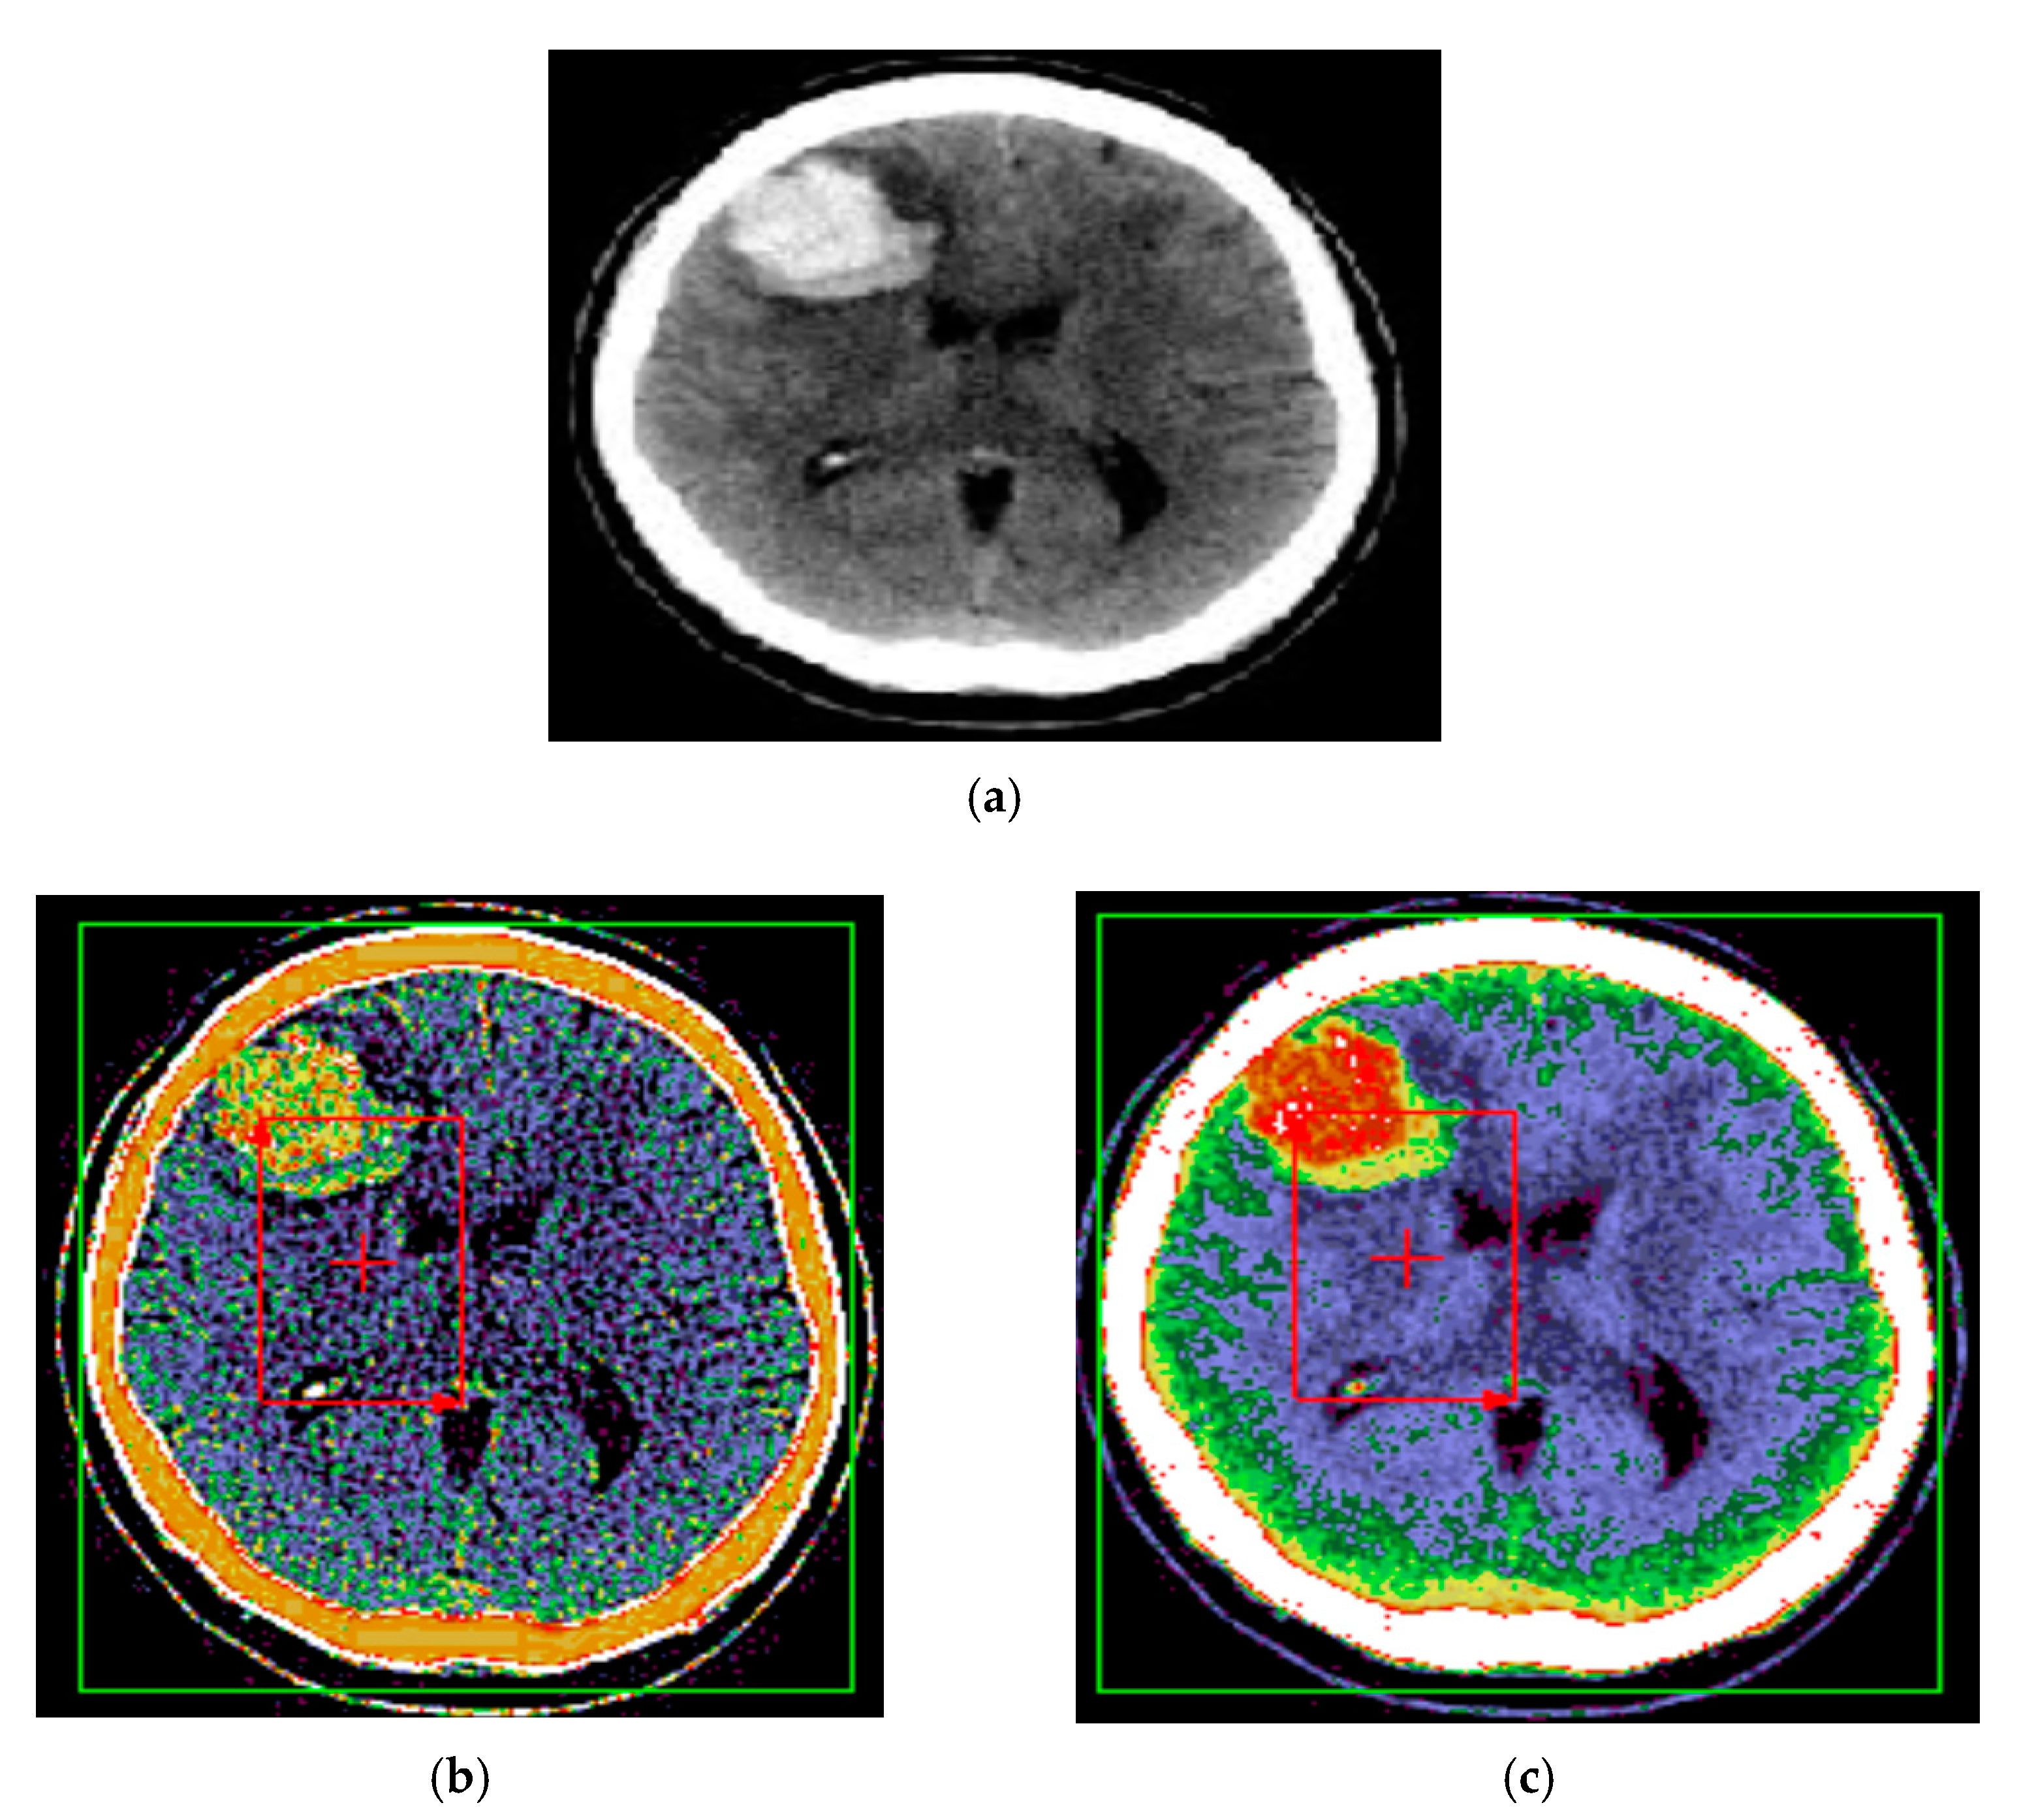

The proposed method for improving images with modified Wiener filter and nonlinear cellular network can be applied with success also with low contrast CT (computer tomograph) images. The improvement of tomographic image quality aims at obtaining superior visibility of the image components, the adaptive increase of the contrast, in order to be interpreted as easily as possible by the specialist doctor. Figure 7, Figure 8 and Figure 9 show the results obtained in the case of such images.

The interest in such filters is determined by the fact that much of the existing information in the images is provided by contours, and most of the noise removal methods cause them to fade. In the present case, at the cost of removing a smaller amount of noise in the contour-containing regions, it can be better preserved, as shown by the results shown in Figure 7, Figure 8 and Figure 9. There is thus a trade-off between the amount of noise removed and the quality of preserving the contours in the image.

It should be noted that in the results presented in Figure 8 and Figure 9, the noise reduction is accompanied by an improvement of the contours of the processed image, leading to a microscopic analysis, highlighting very well the contours of tumor formations from diseased tissues to healthy tissues. Such an estimate is useful for the medical act, especially for surgery. Additionally, the proposed method, in addition to the contour enhancement property, highlights the deconvolution applications for removing or reducing the blurring of energy areas in images by highlighting their vascularization elements (Figure 8 and Figure 9).

Figure 9. (a) Initial image with low contrast; (b) improved image—CT cranial layer image processed with the modified Wiener filter and the nonlinear cellular network.